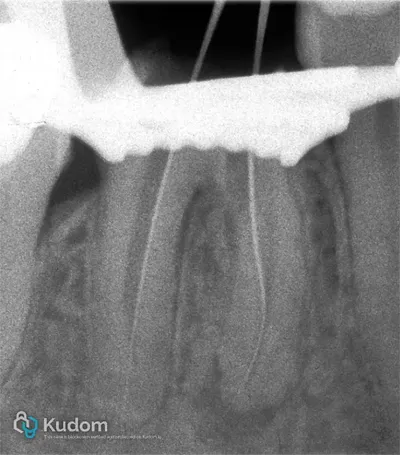

Ritrattamento di un molare inferiore con gestione di perforazione iatrogena a livello della forcazione, sotto l'imbocco radicolare.

Ritrattamento endodontico complesso di un primo molare inferiore con lesione alla forcazione e otturazione di un canale laterale con successivo build-up per overlay a ricopertura cuspidale.